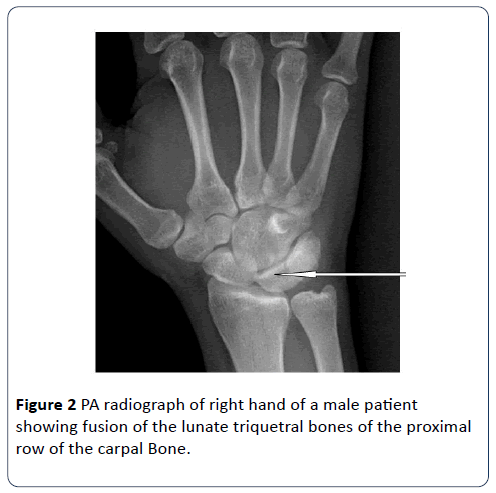

A 42-year-old man presented for radiograph of both hands following pains in the hands. Patient attributed pain to suspected fracture which he presumed he sustained during a squabble with the law enforcement agents. On physical examination, there was no limitation in range of motion of the wrist. There was no swelling or tenderness in the wrist. Other findings were normal. Plain posteroanterior radiographs of both wrists showed bilateral lunotriquetral coalition (Figures 2 and 3).

Figure 2: PA radiograph of right hand of a male patient showing fusion of the lunate triquetral bones of the proximal row of the carpal Bone.